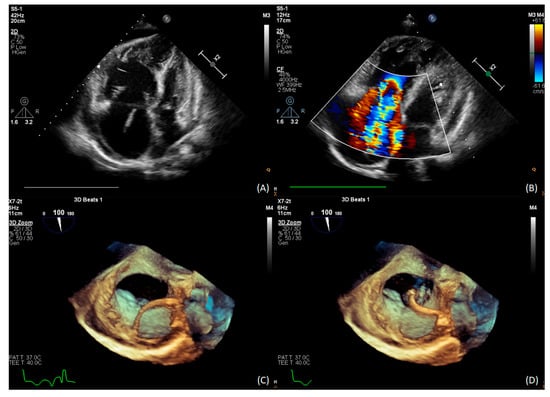

2. Case Presentation